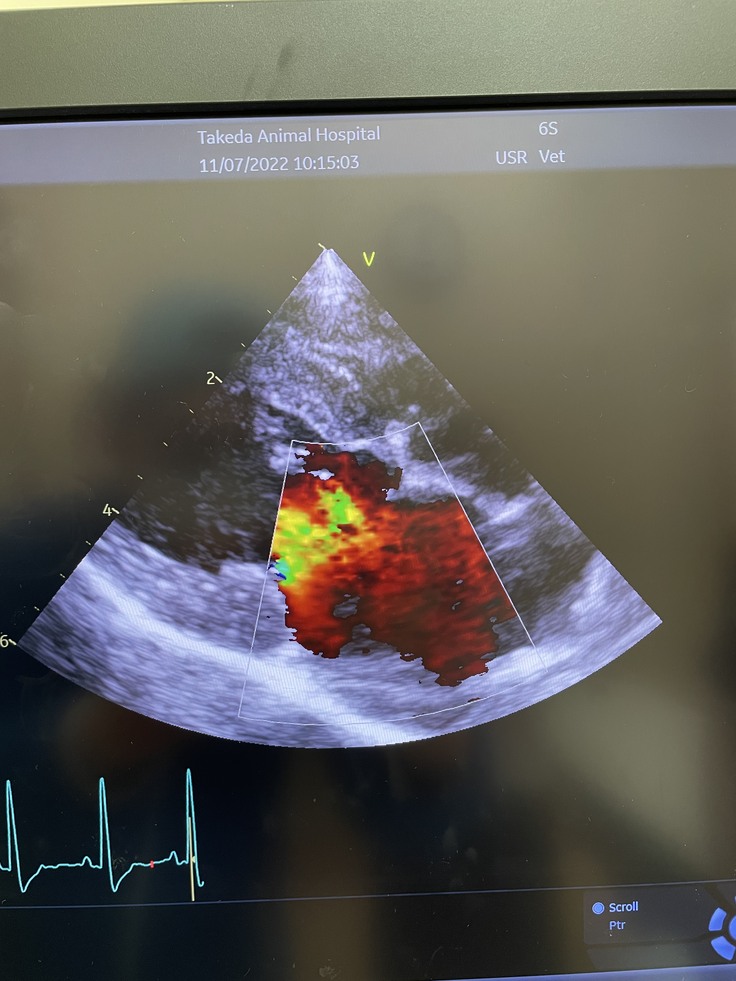

左が健康な心臓です。右が現在のうーちゃんの心臓の状態です。色のついている部分が血液の逆流が見られる箇所になります。僧帽弁閉鎖不全症と診断されてわずか一年ほどで目に見えてわかる程症状が進行していますと主治医の先生から説明がありました。